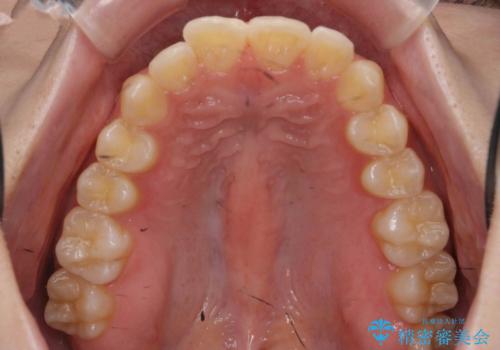

- 突出感のある、前歯の矯正治療を求めて来院されました。

軽度な突出・ガタつきを26枚・約半年の矯正治療期間で計画するインビザラインモデレートプランで治療を始めて行きます。

約半年といった短期間で、前歯の角度やガタつきを改善することができました。